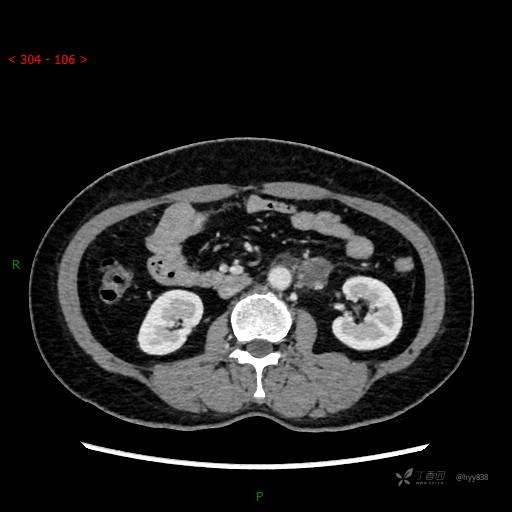

静脉期

CT平扫是外院的,因图像质量原因,不方便上传!